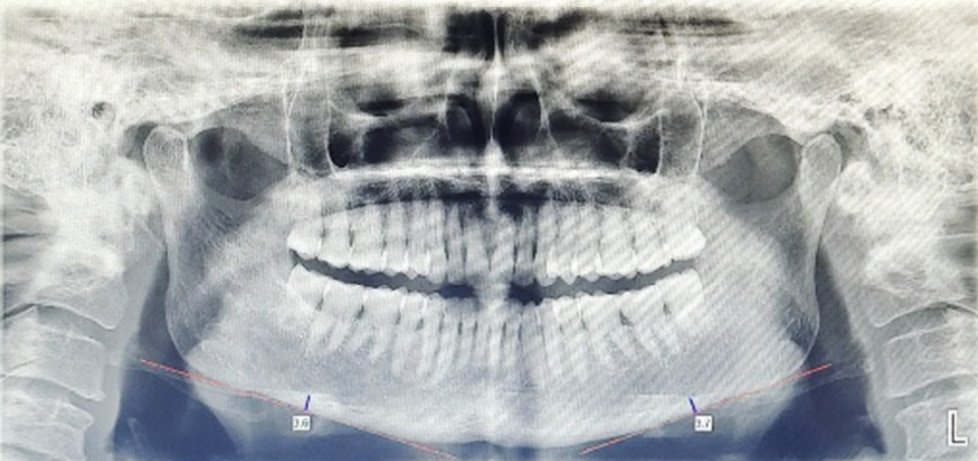

- Ramal notch depth (RND):

Fig. 5. Width of the Ramal notch bilaterally.

It is calculated by drawing a line from ramus tangent line to ramus notch concavity’s deepest point.